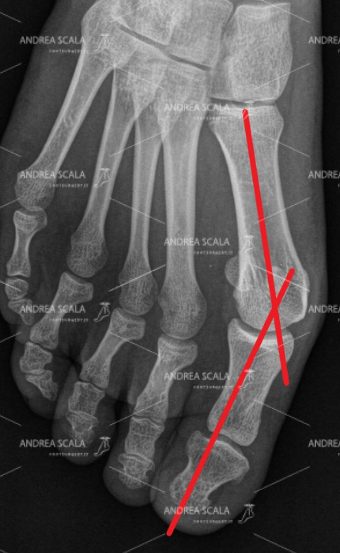

L’alluce valgo consiste in una deviazione del primo metatarso del piede verso l’interno, una situazione che crea un’angolazione anomala dell’alluce e crea una protuberanza “a cipolla” che è causa di forti disagi nella vita quotidiana delle persone che ne soffrono.

L’alluce valgo, infatti, va a premere contro il secondo dito del piede che, nei casi più gravi, tenderà ad accavallarsi col tempo verso le altre dita, deviandole ed assumendo l’aspetto del cosiddetto “dito a martello”. Una situazione che, se non curata e nei casi più gravi, tenderà anche a portare fuori asse l’intero avampiede. Si tratta, quindi, di una vera e propria deformazione del piede che comporta una condizione estremamente dolorosa per i pazienti che ne sono affetti e che va tenuta sotto controllo.